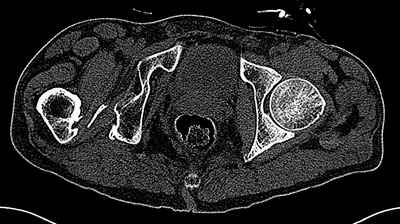

Пациент 30 лет 3 года назад в результате травмы получил травматический

дефект нижних конечностей до в/3 голеней, был пропущен вывих бедра. В настоящее время очень

неплохо ходит на протезах, движения в неоартрозе близки по объему к здоровой стороне.

Основная жалоба - выраженная боль при ходьбе. планируем двухэтапное эндопротезирование -

задним доступом мобилизовать проксимальный отдел бедра, резецировать шейку, аппаратом

низвести бедро(головку оставить там где она есть, так как больших дефектов не видно(может

пригодится в последующем?)). Вторым этапом бесцементное эндопротезирование. Насколько

такой вариант реалистичен? Доступ для второго этапа? Может быть, другие варианты?